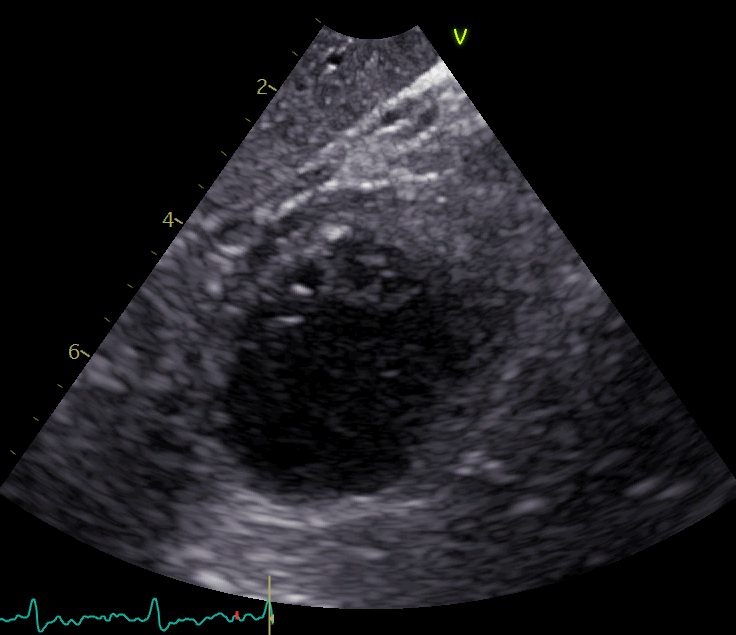

org = cv2.imread(dir+'/im.png')

cv2.imwrite(dir+'/img_.png',org[y:y+h,x:x+w])